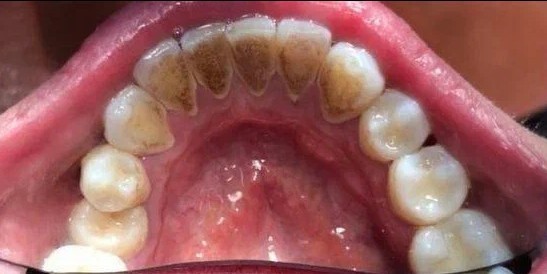

Стоматологическая клиника СКАЙДЕНТ (SKYDENT)

Профгигиена

Доктор: Попова (Михеева) Юлия Васильевна

Доктор: Новлянцева (Новосад) Екатерина Игоревна